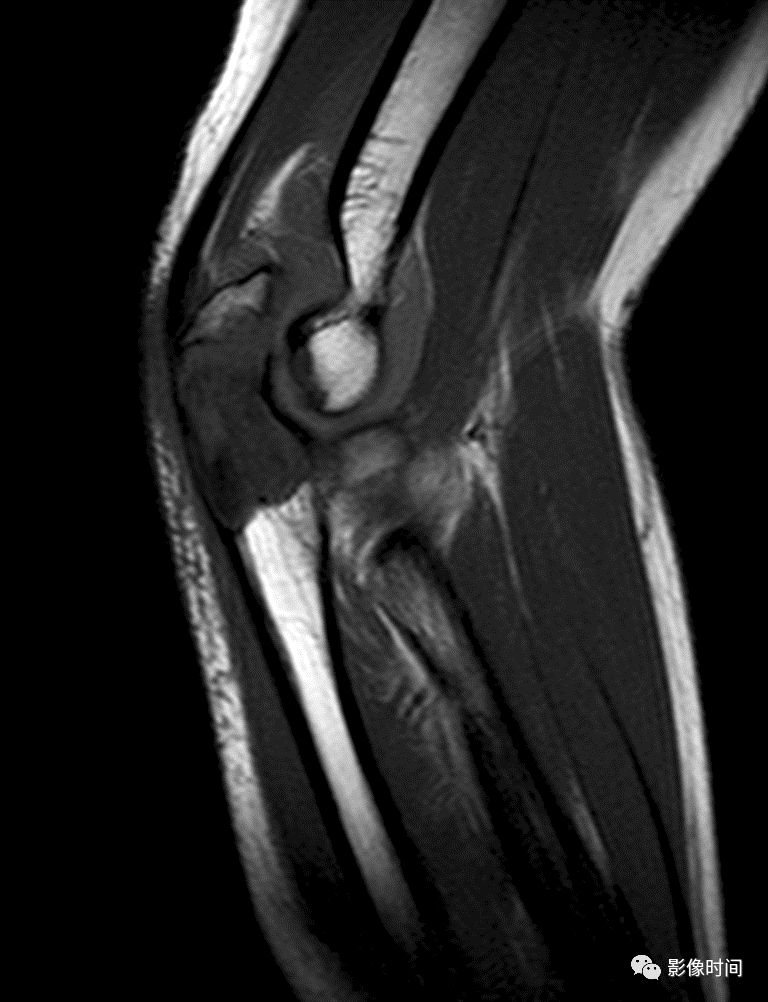

肿瘤对骨骺板和关节软骨的破坏是对骨破坏的继续。缺乏血管的骨骺板对恶性肿瘤有抵抗作用,骨骺板可暂时阻止肿瘤的蔓延,但当肿瘤进一步发展时, 骨骺板亦可被破坏,X 线平片或 CT 可表现为先期钙化带密度减低、中断或消失。MRI 可显示肿瘤从干骺端跨越骨骺板侵犯骨骺(图 15、图 16)。

肿瘤突破关节软骨向关节腔发展时, 可表现为关节面破坏、塌陷(图 17), 关节腔内出现软组织肿块。少数良性骨肿瘤如软骨母细胞瘤, 亦可超越骺板向两侧发展或突入关节腔内, 此为肿瘤膨胀生长所致, 而非浸润性破坏。

图 15  骨骺板破坏:骨肉瘤

图 16  骨骺板破坏:骨肉瘤

图 17  关节软骨破坏:骨肉瘤